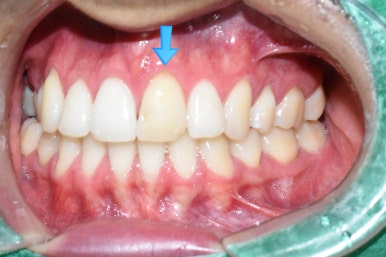

이 외국 환자분은 오래 전에 치아 하나가 변색되기 시작했고

그래서 2년 전 쯤에 본인 나라(유럽)에서 신경치료를 시도 했으나 신경관이 너무 좁아서 신경관을 찾지 못해

중단된 상태였습니다.

위 앞니 하나가 아주 변색이 된 상태 (치료 전)

변색된 앞니

딱 눈에 보이는 가장 큰 앞니 하나가 변색이 너무 심하니

본인 나라에서 마무리하지 못한 신경치료에 대해

마무리를 하고 뚫어서 신경치료한 윗부분을 레진으로 메운 후

치아는 전체적으로 깎아서 크라운을 하게 되었습니다.